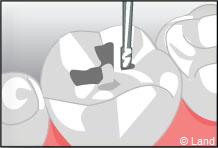

Inconvénient mineur : sauf dans certains cabinets équipés en CFAO (Conception et Fabrication Assistées par Ordinateur), cette technique nécessite 2 séances de soins, car une étape de laboratoire s’intercale entre la réalisation de la cavité et la pose et le scellement des inlays onlays réalisés en métal, en résine composite ou en céramique.

Exemple d’un onlay molaire